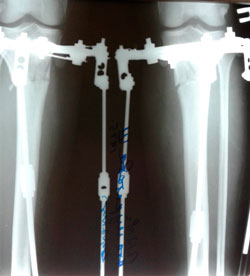

Перед крутками.

IMG-20181128-WA0023.jpg

IMG-20181128-WA0014-(1).jpg